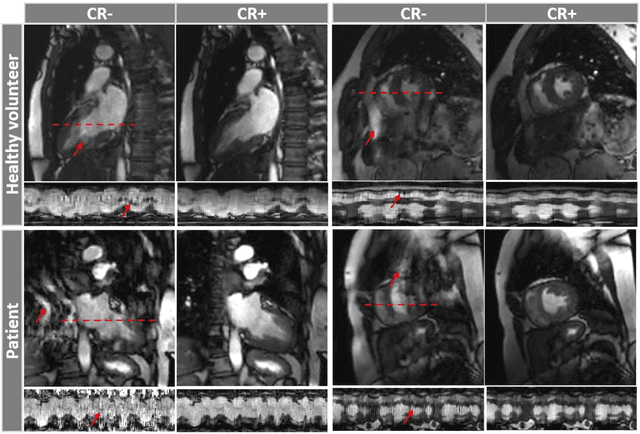

Abstract:Background: Accelerated real-time cine (RT-Cine) imaging enables cardiac function assessment without the need for breath-holding. However, when performed during in-magnet exercise, RT-Cine images may exhibit significant motion artifacts. Methods: By projecting the time-averaged images to the subspace spanned by the coil sensitivity maps, we propose a coil reweighting (CR) method to automatically suppress a subset of receive coils that introduces a high level of artifacts in the reconstructed image. RT-Cine data collected at rest and during exercise from ten healthy volunteers and six patients were utilized to assess the performance of the proposed method. One short-axis and one two-chamber RT-Cine series reconstructed with and without CR from each subject were visually scored by two cardiologists in terms of the level of artifacts on a scale of 1 (worst) to 5 (best). Results: For healthy volunteers, applying CR to RT-Cine images collected at rest did not significantly change the image quality score (p=1). In contrast, for RT-Cine images collected during exercise, CR significantly improved the score from 3.9 to 4.68 (p<0.001). Similarly, in patients, CR did not significantly change the score for images collected at rest (p=0.031) but markedly improved the score from 3.15 to 4.42 (p<0.001) for images taken during exercise. Despite lower image quality scores in the patient cohort compared to healthy subjects, likely due to larger body habitus and the difficulty of limiting body motion during exercise, CR effectively suppressed motion artifacts, with all image series from the patient cohort receiving a score of four or higher. Conclusion: Using data from healthy subjects and patients, we demonstrate that the motion artifacts in the reconstructed RT-Cine images can be effectively suppressed significantly with the proposed CR method.